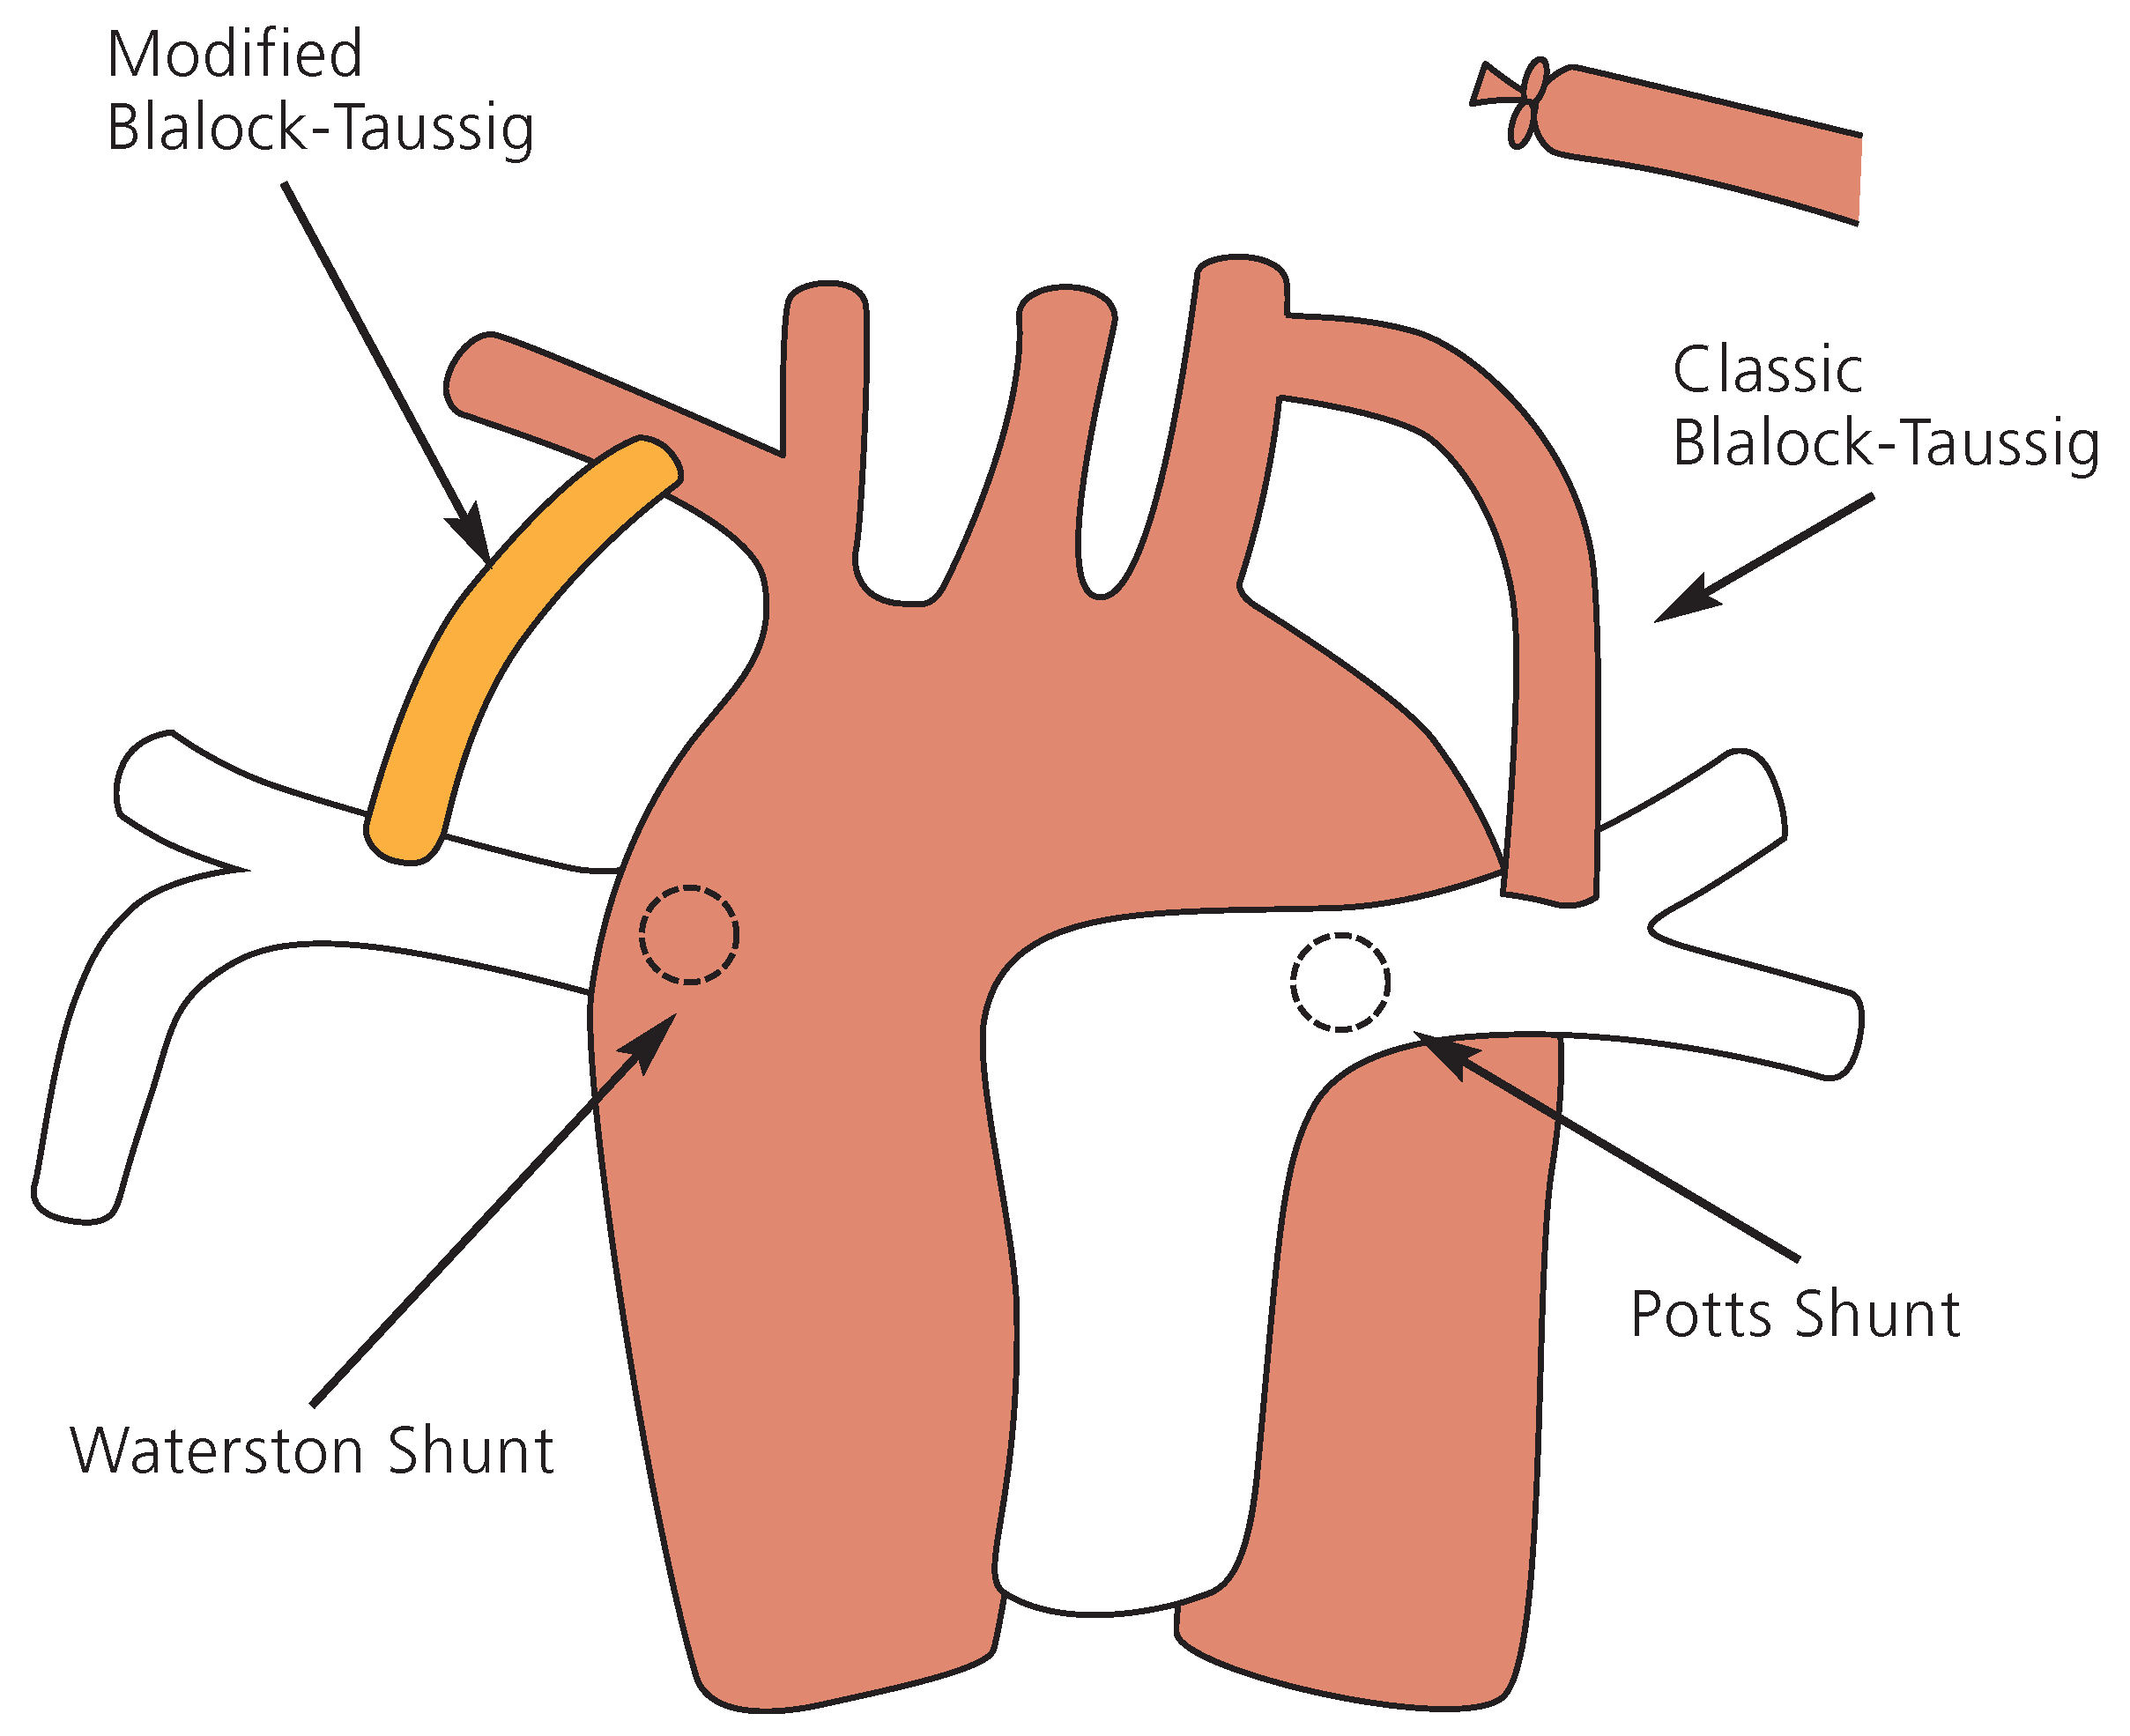

Die erwähnte Ablehnung von Helen Taussig gegenüber Lillehei’s Eingriffen mit «Controlled Cross Circulation» und ihrer potentiell 200%-Mortalität beruht auf der Tatsache, dass bereits zum damaligen Zeitpunkt mittels palliativ angelegtem aorto-pulmonalem Shunt das Überleben der «blue babies» deutlich verbessert werden konnte. Helen Taussig hatte in den 1930er Jahren beobachtet, dass sich der Zustand von zyanotischen Neugeborenen zum Zeitpunkt des spontanen Ductus-Botalli-Verschlusses oft verschlechterte. Sie war überzeugt, dass das Anlegen eines «künstlichen» Ductus Botalli die Klinik gewisser zyanotischer Patienten verbessern könnte. Diese Idee diskutierte sie mit Alfred Blalock, einem Chirurgen aus Baltimore. Alfred Blalock hatte zuvor vergeblich versucht, durch die Anastomose der Arteria subclavia auf die Lungenarterie beim Hund ein Modell einer Shunt-induzierten pulmonalen Hypertonie zu entwickeln. Diese glückliche Fügung führte am 29. November 1944 zum Anlegen der ersten chirurgisch kreierten aorto-pulmonalen Verbindung bei Fallot-Patienten, dem klassischen Blalock-Taussig-Shunt (

Abb. 3). Die Lungendurchblutung wurde durch eine End-zu-Seit Anastomose der A. subclavia auf die entsprechende linke (beim Arcus aortae sinister) oder rechte (beim Arcus aortae dexter) Lungenarterie verbessert [

Die Nachteile dieser Anastomose waren die Volumenbelastung des linken Ventrikels sowie eine nun von Kollateralen abhängige Perfusion des entsprechenden Armes. Letzteres konnte ab den 1970er Jahren durch die Interposition eines Gore-Tex-Shunts zwischen A. subclavia und A. pulmonalis (modifizierter Blalock-Taussig-Shunt) anstelle der direkten End-zu-Seit-Anastomose vermieden werden.

Die Potts- und Waterston-Anastomose wurden 1946 bzw. 1962 eingeführt, und beinhalteten eine direkte Anastomose der linken oder rechten Lungenarterie mit der benachbarten Aorta descendens (Potts-Anastomose,

Abb. 3) oder Aorta ascendens (Waterston-Anastomose,

Abb. 3). Diese Anastomosen wurden im späteren Verlauf vermieden, da sie einerseits im Rahmen des Körper-Wachstums oft zu einer Distorsion der mit der Aorta verbundene Lungenarterie und dadurch zu Stenosen führten und andererseits der letztendlich geschaffene Anastomosen-Diameter für den Chirurgen nur beschränkt voraussehbar war. Vernarbung konnte die Anastomose sowohl vergrössern als auch verkleinern mit dem Risiko einer pulmonalen Hyperzirkulation und irreversiblen pulmonalen Hypertonie bzw. einer anhaltenden pulmonalen Hypoperfusion.